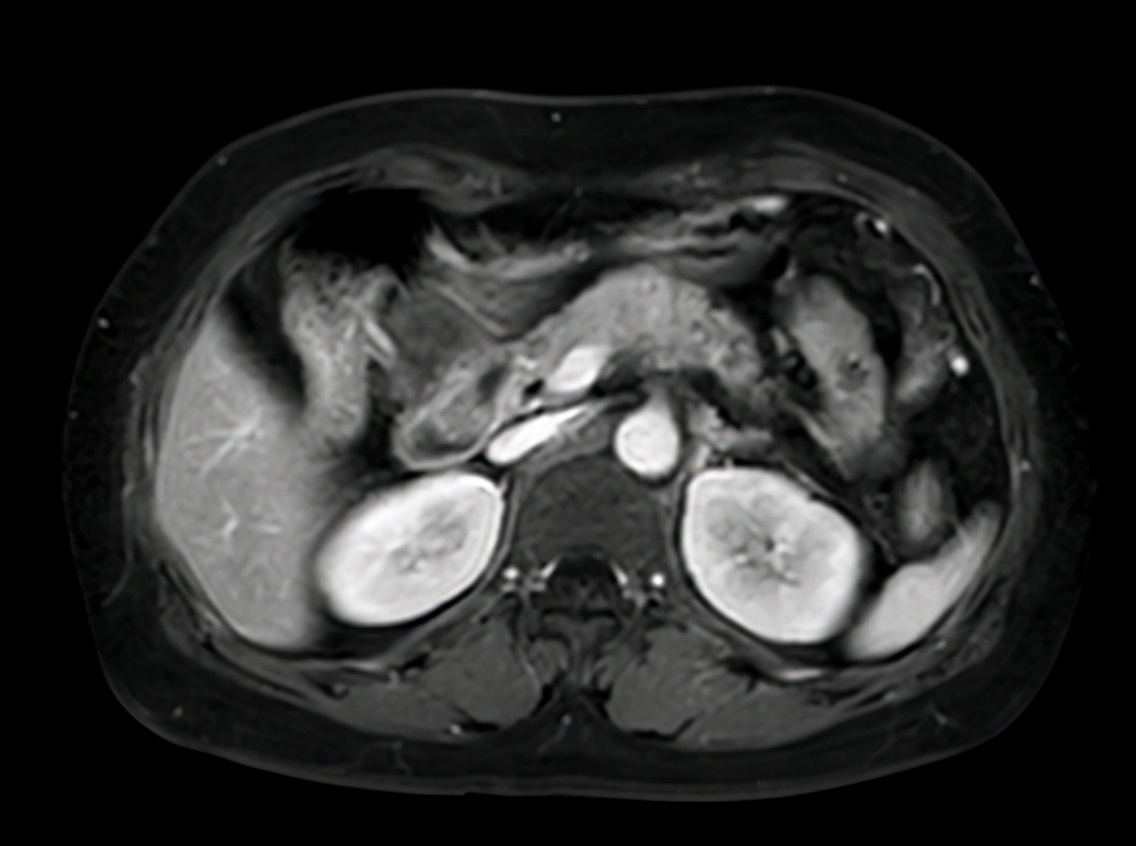

入院以后还需要进一步了解肿瘤的大小、部位、是否有侵犯到其他器官等,完善了腹部增强CT、胸部CT和超声胃镜等检查。CT胸部平扫(2019-08-16 13:21):左肺微小结节,左肺纤维灶。CT上腹部平扫+增强(2019-08-20 16:39):胰腺颈体部胰腺癌伴脾动脉受侵考虑,脾静脉可疑受侵。 腹膜后多发稍肿大淋巴结。MR(磁共振)上腹部平扫+增强+MRCP(2019-08-17 15:49):胰腺颈体部占位(考虑胰腺癌),病变侵犯脾血管、腹腔干分叉部;腹膜后多发稍肿大淋巴结。ES(内镜)超声胃镜(2019-08-21 15:20):胰颈低回声病灶。

2019-8-17上腹部增强MRI